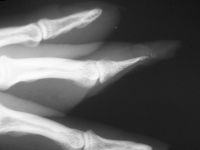

| Case

3. This gentleman sustained partial amputations of all fingers in an industrial press. His index finger was the only digit with a potentially salvageable fingertip. |